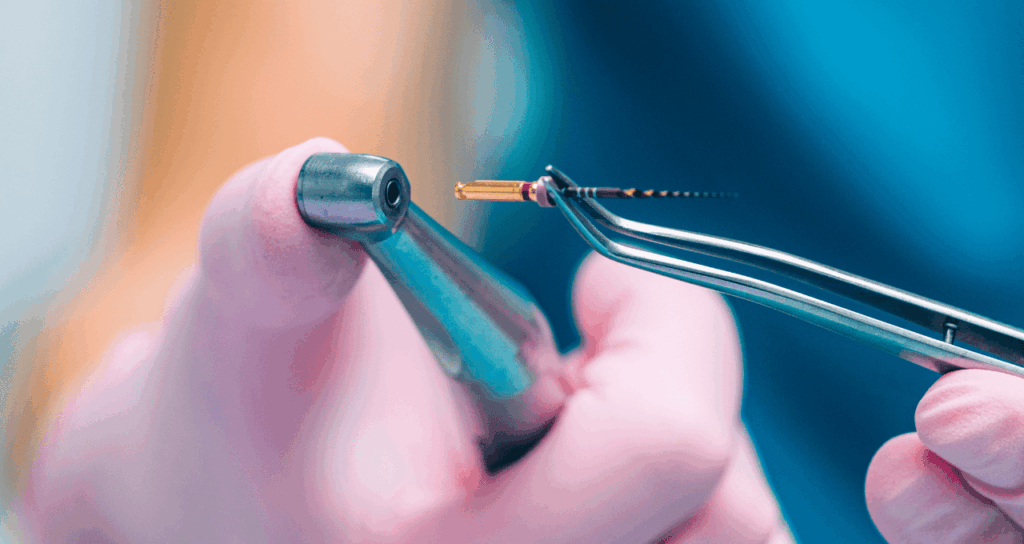

複雑な形状に追従する「ニッケルチタンファイル」

根の中の汚れを削り取るための器具を「ファイル」と呼びます。

従来はステンレス製のファイルが主流でしたが、硬くてしなりにくいため、湾曲した根管の中で無理に進めると本来の形を変えてしまったり突き破ってしまったりするリスクがありました。

当院では、非常に柔軟性に優れた「ニッケルチタンファイル」を使用しています。

このファイルは、形状記憶合金の特性を持っており、大きく曲がった根管にもしなやかに追従します。

専用の「エンドモーター(電動制御装置)」に装着して使用することで、一定の回転数とトルク(力)で安全に汚染部分だけを除去することが可能です。

根管の形態を損なうことなく、スピーディーかつ確実に清掃を行います。